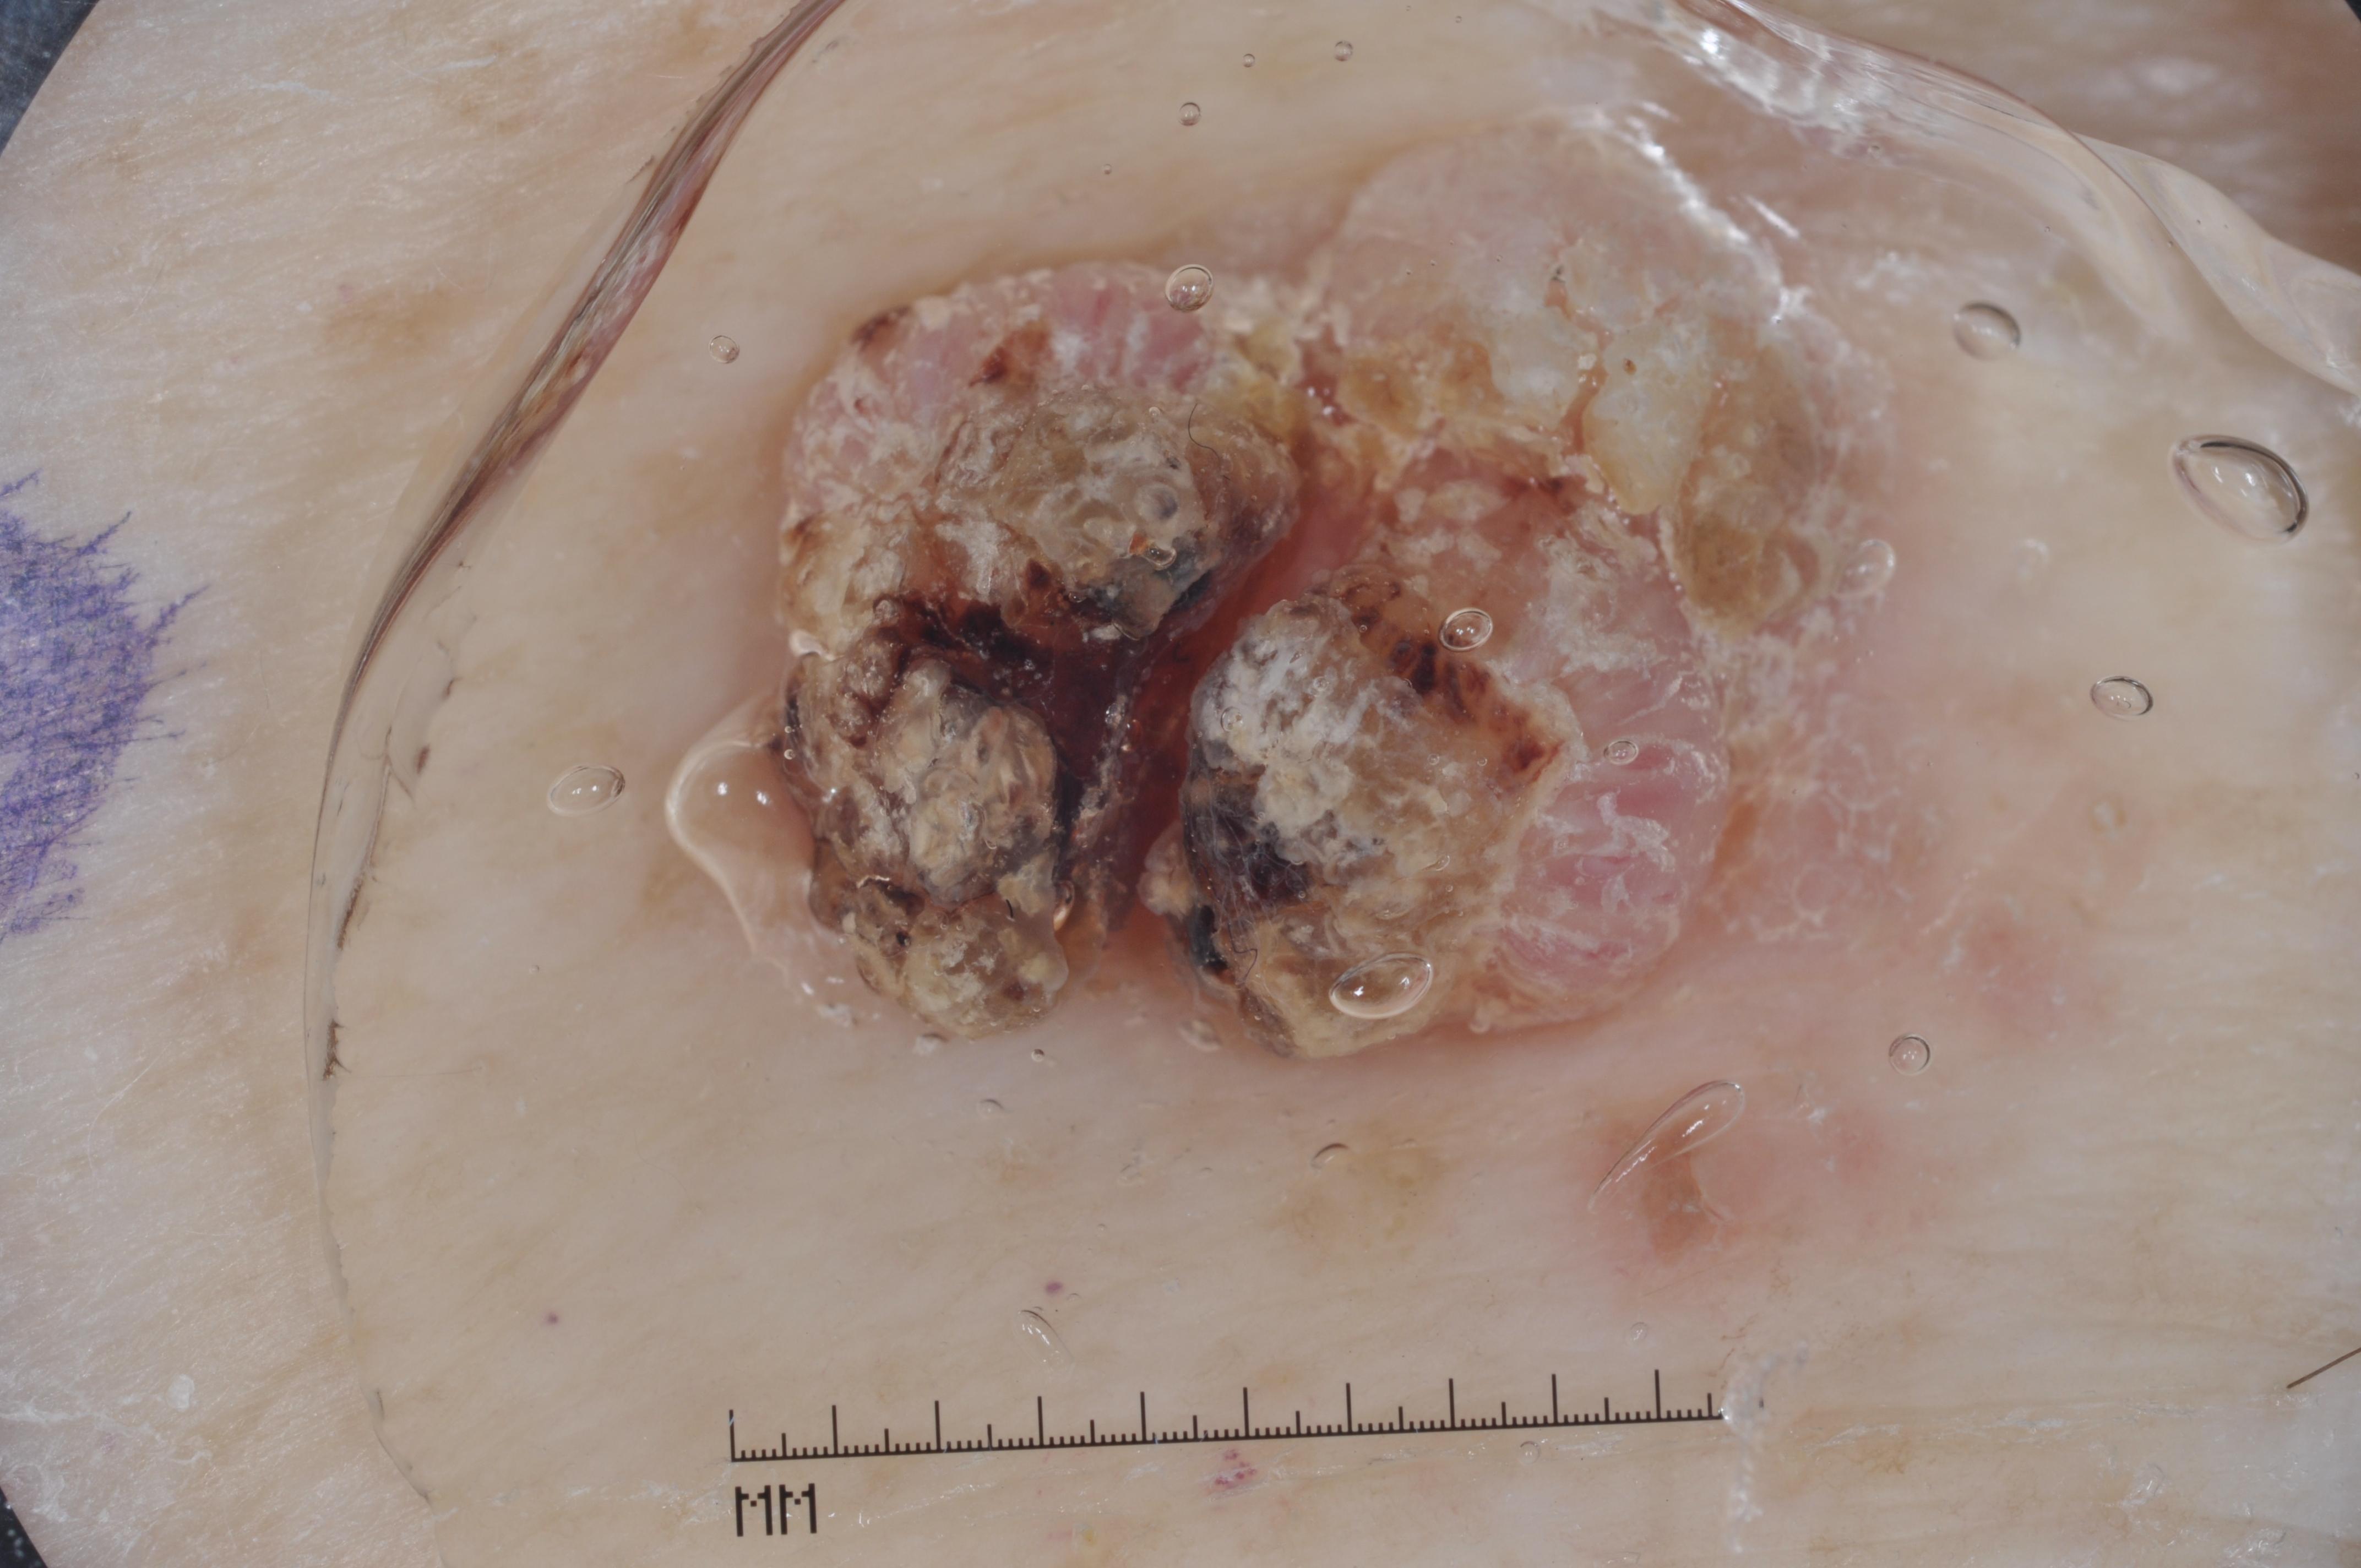

{

"age_approx": 85,

"anatom_site_general": "anterior torso",

"concomitant_biopsy": true,

"dermoscopic_type": "contact non-polarized",

"diagnosis_1": "Malignant",

"diagnosis_2": "Malignant epidermal proliferations",

"diagnosis_3": "Squamous cell carcinoma, NOS",

"diagnosis_confirm_type": "histopathology",

"image_type": "dermoscopic",

"lesion_id": "IL_0167400",

"melanocytic": false,

"sex": "male"

}